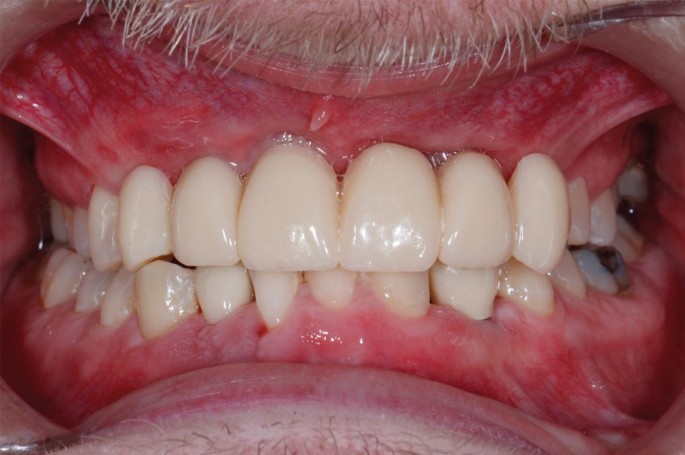

Six months later, restoratively driven implant placement with four implants in the maxilla and two in the mandible at an insertion torque of 35 Ncm was undertaken (Fig. 6). Despite the fibrous nature of the bone, high primary stability was achieved and healing one week later was uneventful. A provisional bridge was fitted five months after the surgery in the maxilla and crowns fitted in the mandible (Fig. 7). The radiographs taken post-fit (Fig. 8) showed the ground-glass bone appearance. The radiolucency seen on the distal of the lateral incisor implants could be the healing response of the CFD as clinically there was no pocketing, bleeding or inflammation noted around the implants. The patient was delighted with the outcome.

Case 1: upper implant-supported bridge and lower right and left implant-supported crowns in situ

(A, B) Case 1: peri-apical radiographs showing the implants placed in the anterior maxilla